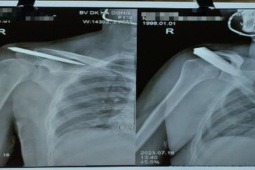

Hung khí nhóm Phúc dùng đuổi, chém đối thủ

Được bạn rủ đi giải quyết mâu thuẫn, L đồng ý và sau đó bị chém thương tích 47%.